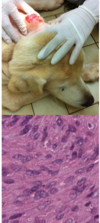

Sarcoptic Mange

Sarcoptes scabiei

Pathogenesis of sarcoptic mange

- Burrow into stratum corneum

- Intesnse pruritis through hypersensitivity mechanism

- Self trauma, chronic irritation

- Hyperkeratosis, lichenification, alopecia